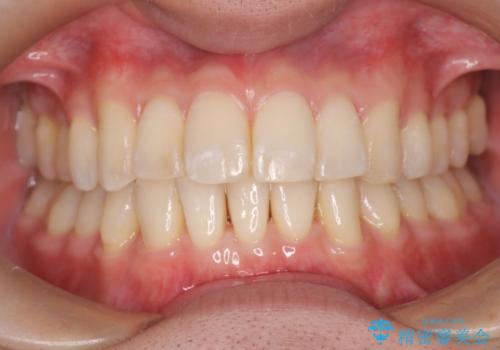

前歯の重なりとガタガタをマウスピースで改善した症例

初診時の歯並びの状態としては、上下ともに前歯部の中等度のがたつきがあり、上の前歯が重なっている状態でした。

また元々下の前歯は1本少なく、歯の本数が少ないことを前提とした矯正治療を行いました。

抜歯は必要なく、マウスピース矯正にて治療を行っています。

見た目、嚙み合わせ及び、治療期間や施術内容に大変ご満足いただきました。